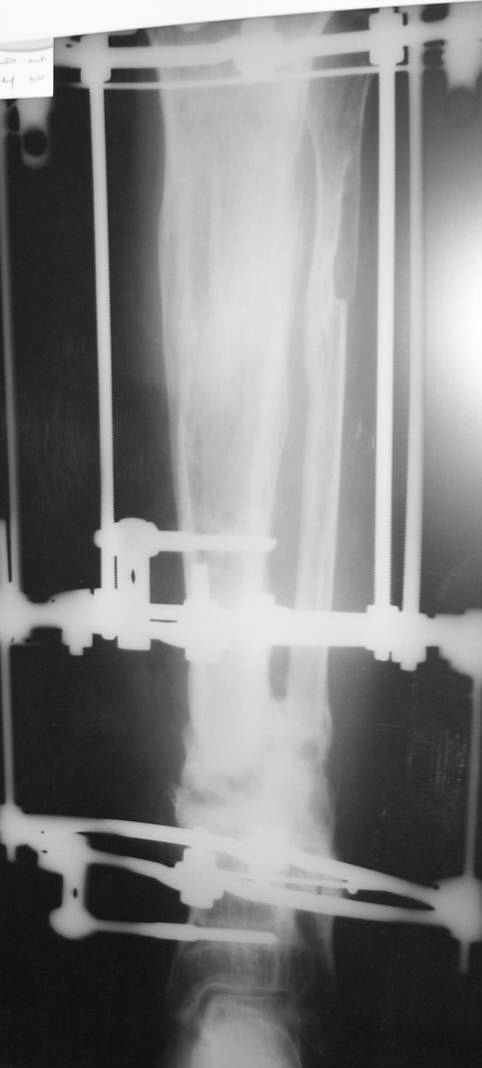

This Patient have to be treated by using Ilizarov bifocal bone transport, aproximatly as showen here.

You can do it like this also...